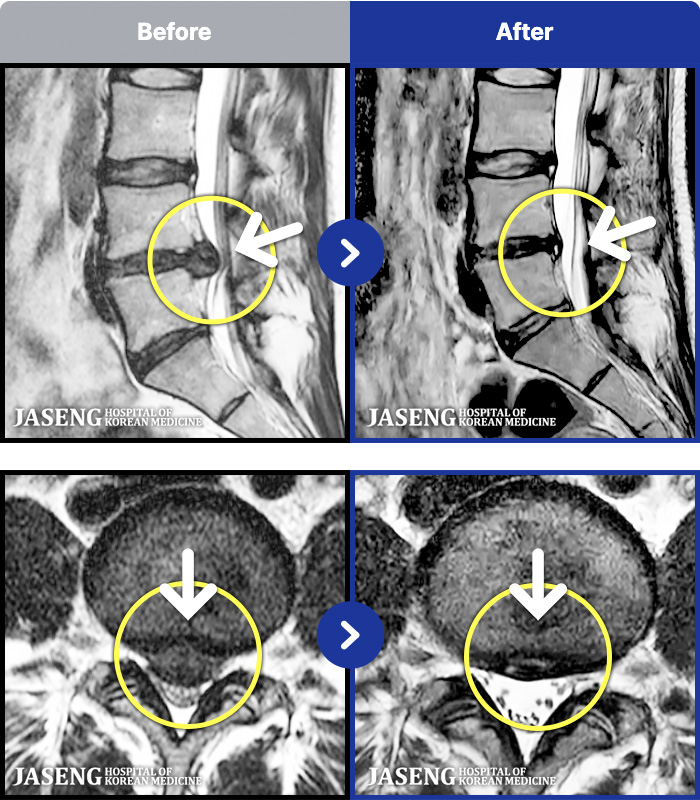

MRI ġ

1,237 MRI ũ ʸ Ȯϼ.